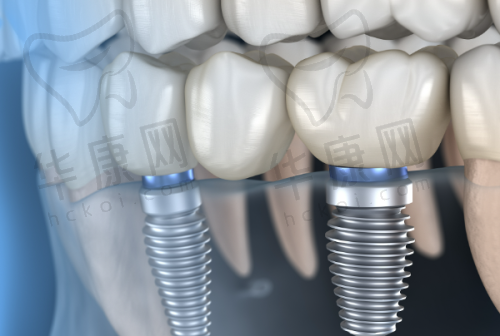

该口腔门诊部主打德系种植技术,在瑞士ITI种植牙方面有着独特的优势。其擅长即刻种植和微创种植技术。即刻种植技术可以在拔牙后立即进行种植,大大缩短了患者的治疗周期,减少了多次就诊的麻烦。而微创种植则是通过微小的切口进行种植手术,对患者的创伤小,术后修复快,患者在术后的疼痛感也相对较轻。比如,曾经有一位患者在溧水瑞齿固德口腔进行瑞士ITI种植牙,采用微创种植技术,术后当天就能正常饮食,修复速度超出了患者的预期。

医院拥有新型的设备,为瑞士ITI种植牙手术提供了精细的保护。精良的口腔CT设备可以清晰地显示患者口腔内部的结构,帮助医生更正确地了解患者的牙槽骨情况,从而制定出更合适的种植方案。在手术过程中,使用的种植器械也都是经过严格筛选的,确保手术的安心性和成功几率。例如,通过精良的设备,医生可以严谨地控制种植体的植入位置和角度,提高种植牙的稳定性和美观度。